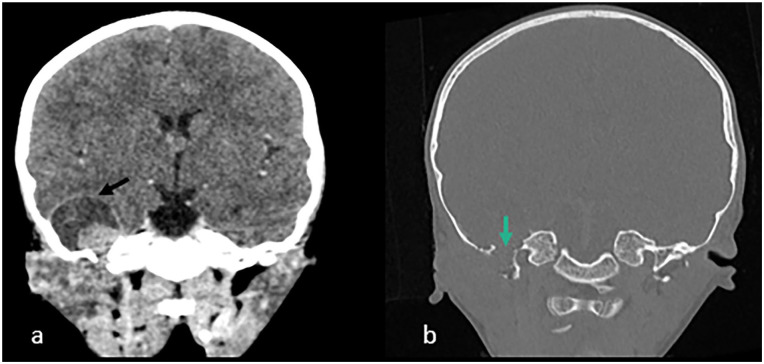

Infantile myofibromatosis is a proliferative disorder occurring during infancy and early childhood, marked by the development of nodular or diffuse lesions consisting of various mesenchymal elements. Intracranial involvement is infrequently reported. Here, we present the case of a 3-year-old girl exhibiting a rare manifestation of IM with intracranial parenchymal involvement, displaying a histological pattern documented in existing literature on patients with infantile myofibromatosis. Subsequent MRI follow-up revealed no signs of recurrence.